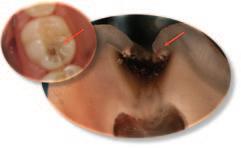

Table 1: Merged-ICDAS visual coronal caries stages.4

Merged-ICDAS score Code Description

Sound (ICDAS 0) 0

Initial caries lesions (ICDAS 1-2) A

No evidence of change in enamel translucency due to caries after plaque removal and air drying

Changes in enamel seen as a caries opacity or visible discolouration (white/brown spot) not consistent with clinical appearance of sound enamel, with no evidence of surface breakdown, no underlying dentine shadowing and no cavitation

Moderate caries lesions (ICDAS 3-4) B3

White/brown spot lesion with localised microcavity/discontinuity, without visible dentine exposure. Best seen after air drying B4 Obviously discoloured dentine visible through apparently intact or microcavitated enamel surface, which originated on the surface being evaluated. Often seen easiest with the tooth surface wet

Extensive caries lesions (ICDAS 5-6) C Obvious visible dentine cavity in opaque/discoloured enamel. A WHO/CPI/PSR probe can gently confirm if the cavity extends into dentine

2. Assess the staging of the coronal carious lesion